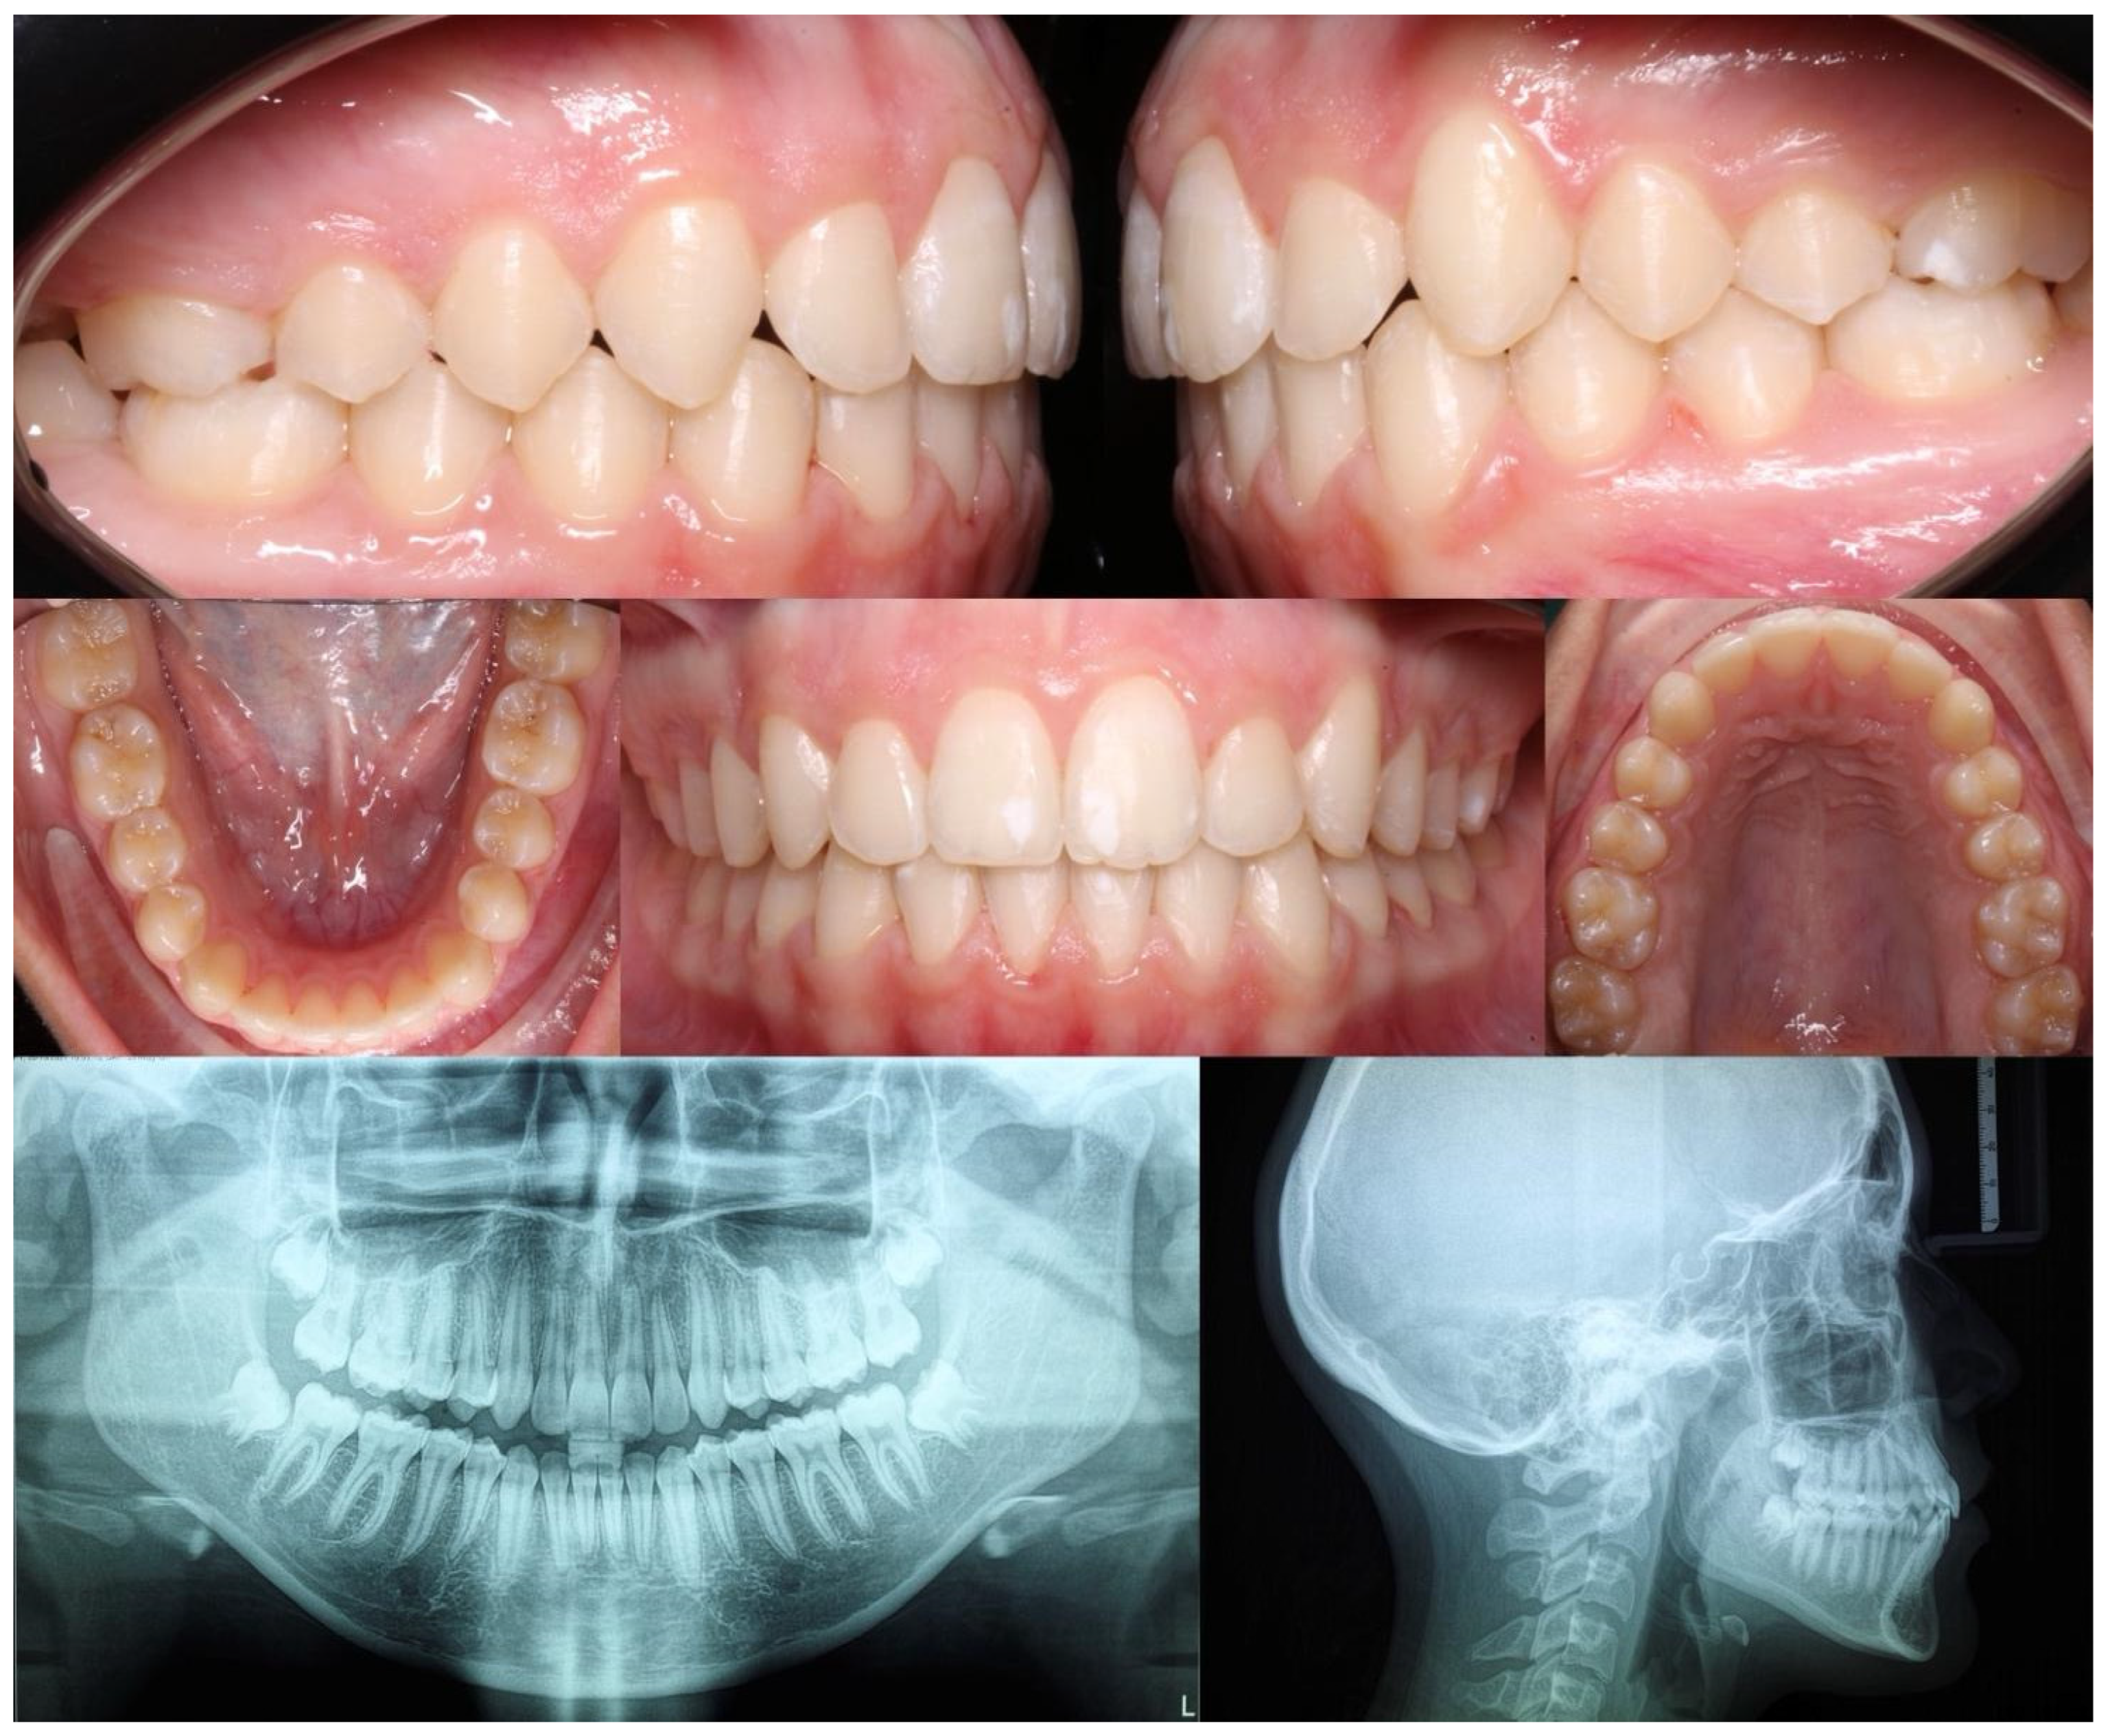

Figure 3.

Final right, left, front, upper, and lower orthopantomography and lateral cephalometric radiographs.